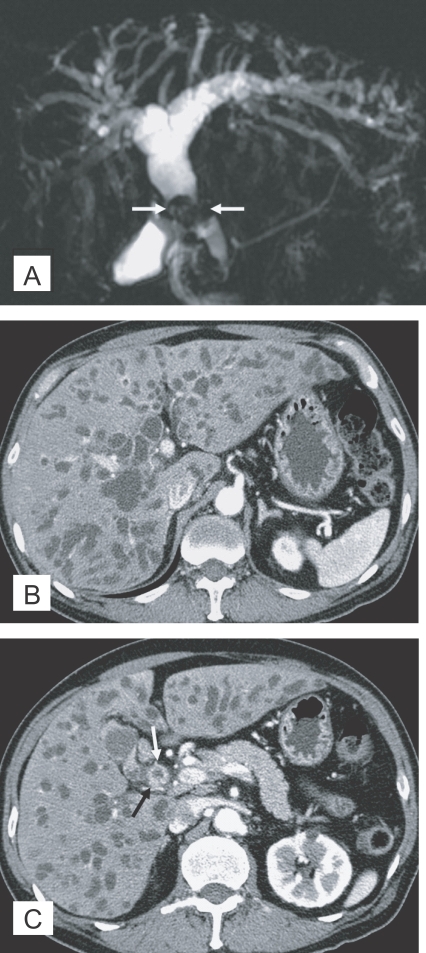

Fig. 6

Cholangiocarcinoma in the mid common duct, with clonorchiasis, in a 64-year-old man. A. MR cholangiography shows a diffuse dilatation of the intrahepatic bile ducts and common duct. Note an intraluminal tumor (arrows) at the level of the mid common duct. B. Contrast-enhanced CT shows diffuse and marked dilatation of the intrahepatic bile ducts. C. CT at a level lower than (B) shows the enhancing, segmental thickened wall (arrows) of the mid common duct, which represents an extrahepatic cholangiocarcinoma.

Fig. 6 Cholangiocarcinoma in the mid common duct, with clonorchiasis, in a 64-year-old man. A. MR cholangiography shows a diffuse dilatation of the intrahepatic bile ducts and common duct. Note an intraluminal tumor (arrows) at the level of the mid common duct. B. Contrast-enhanced CT shows diffuse and marked dilatation of the intrahepatic bile ducts. C. CT at a level lower than (B) shows the enhancing, segmental thickened wall (arrows) of the mid common duct, which represents an extrahepatic cholangiocarcinoma.

The imaging findings of clonorchiasis-associated cholangiocarcinomas are combinations of the findings of the 2 diseases (Figs. 5 and 6) (Choi et al., 2004). Diffuse dilatation of peripheral intrahepatic ducts is attributed to changes that are secondary to clonorchiasis, and segmental and severe dilatation around the tumor is caused by obstruction by the tumor (Fig. 5) (Choi et al., 1988 & 1989). Extrahepatic cholangiocarcinomas, associated with clonorchiasis, show diffuse dilatation of the peripheral and central intrahepatic bile ducts (Fig. 6). When an extrahepatic cholangiocarcinoma is not associated with clonorchiasis, dilatation of the peripheral intrahepatic bile ducts is not conspicuous (Fig. 7). After the development of the distal obstruction due to an extrahepatic cholangiocarcinoma, pre-existent dilated intrahepatic bile ducts with clonorchiasis easily progress the dilatation.